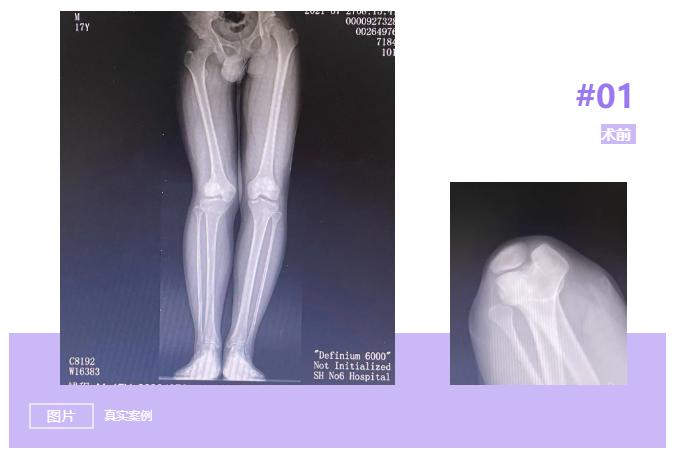

小钱今年17岁,在5年前因车祸导致右膝关节髌骨骨折,在当地医院进行了“石膏固定”治疗。后期康复锻炼时出现右膝关节活动障碍,膝关节疼痛,同时伴有膝关节屈曲受限,经药物等保守无效。为求进一步诊治,小钱慕名来到上海市第六人民医院就诊。门诊摄片提示:双下肢欠对称,骨盆右倾,右膝外翻,右髌骨脱位可能。门诊拟“右膝关节损伤、右髌骨脱位”收入病房。

关节外科刘万军主任针对小钱的病情,分析他多年来膝关节疼痛的原因是因为右下肢外翻畸形导致膝关节外侧间隙压力增加,软骨磨损严重,导致外侧间隙变窄、疼痛,临床表现为外侧骨性关节炎;另外髌骨脱位也导致伸膝装置的挛缩和髌骨外侧结构的挛缩。长期的疼痛和关节畸形,导致长短腿,让小钱的骨盆出现倾斜,继而会出现脊柱侧弯,高低肩等等一系列问题。

考虑患者年龄尚轻,可进行股骨远端闭合截骨术(DFO)纠正下肢力线,将膝关节负重中心内移,减少外侧间室的压力来改善症状,延缓患者关节置换的时间或者避免关节置换。

经与患者及家属沟通后,其表示选择保膝手术,经过术前仔细测量计算,确定手术方案后,刘万军主任带领团队给患者进行了“右股骨远端内侧闭合截骨术”。